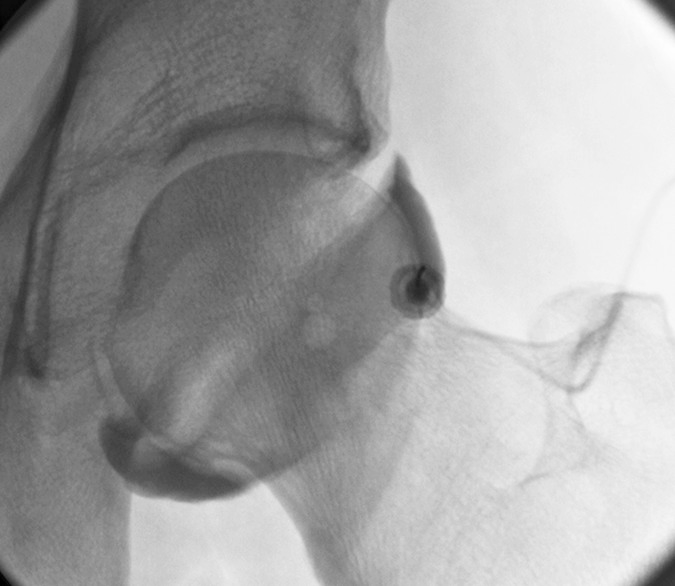

Hip¶

- Hip is internally rotated

- Easiest is lateral edge of bone but can also target lateral cortex and sliding along 2-3mm after making contact for a paracortical approach

- Lateral aspect targeted to avoid neurovascular structures and iliopsoas tendon

- Anterior and paracortical approaches respectively: